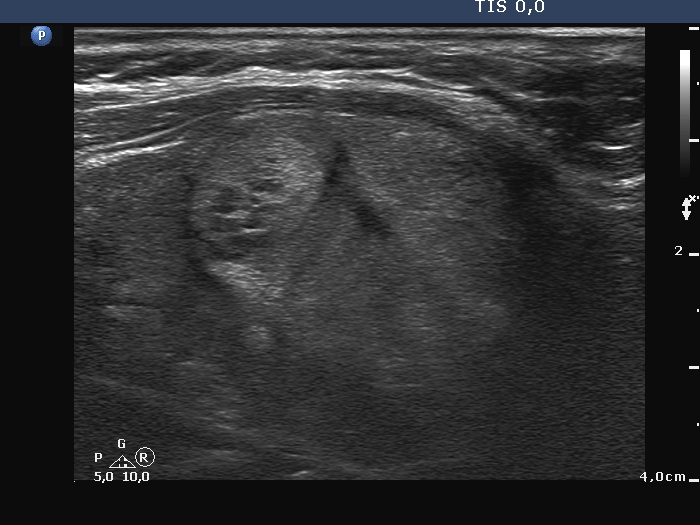

The operated thyroid - case 1388 (ultrasonographic picture 4)

Right lobe, longitudinal scan

Right lobe, another longitudinal scan. The lobe has other, much smaller discrete lesions.